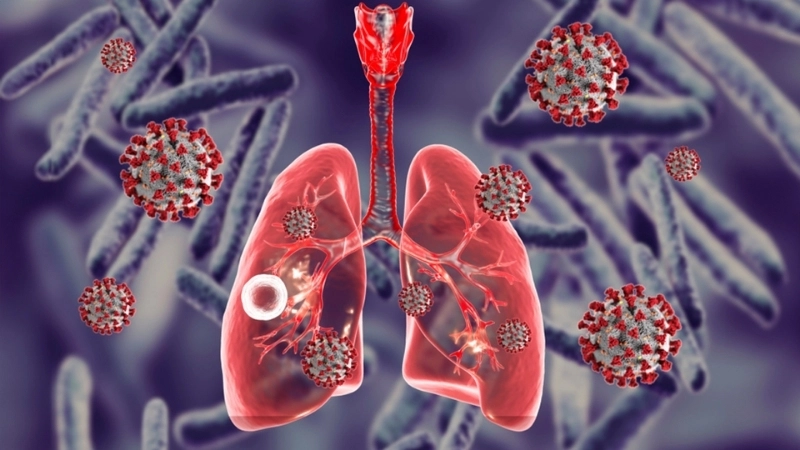

• Nguyên nhân trực tiếp gây bệnh là do vi khuẩn lao có tên khoa học là Mycobacterium tuberculosis (MTB) tấn công và gây tổn thương tại nhu mô phổi.

• Vi khuẩn lao lây truyền chủ yếu qua đường không khí khi người bệnh ho, hắt hơi, khạc nhổ, tạo ra các hạt bụi nhỏ chứa vi khuẩn trong không khí.